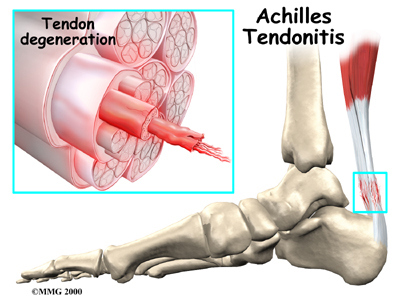

However, tendons do not always become inflamed as a result of an injury. A condition called tendinopathy—in which collagen gradually begins to degenerate or break down over time—may also lead to tendon damage. Nonetheless, tendonitis is still the most commonly used term to describe tendon inflammation.

Insertional Achilles tendonitis refers to damage of the lower part of the tendon where it inserts (attaches) to the heel bone. This form of tendonitis is common in runners. Non-insertional Achilles tendonitis occurs when collagen fibers in the middle of the tendon begin to develop microscopic tears, usually due to wear and tear. Younger active individuals (athletes) tend to experience this type of tendonitis.

The aging process can also lead to tendon damage. As individuals age, connective tissues within the tendon can break down or degenerate. More specifically, age-related tendon problems usually involve the degeneration of collagen. As the tissue damage progresses, pain and inflammation may alter joint mobility. Health care professionals refer to this type of issue as tendonosis.

Some researchers believe that decreased blood flow to the tendons can cause the tissue damage that leads to tendonosis. Reduced blood flow prevents sufficient amounts of oxygen and nutrients from reaching the tendons. This causes collagen fibers to become weak and lose their rope-like structure. Damage due to degeneration is particularly common in the rotator cuff, the Achilles tendon, and tendons in the elbow.

However, different factors may simultaneously cause tendonitis or tendonosis. For instance, a woman in her forties who takes up running may develop joint inflammation due to the age-related degeneration of collagen in the joints in combination with the mechanical stress of running.